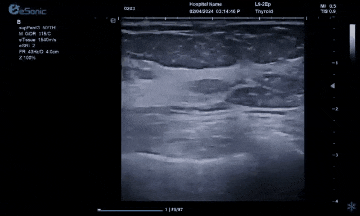

对于乳腺结节相关的自动检测功能,乳腺结节病灶检出率≥95%、良恶性分类灵敏度≥90%、良恶性分类特异度≥85%。